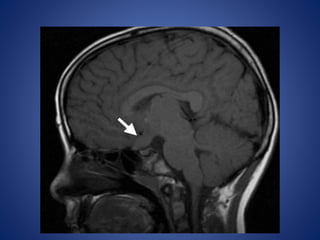

Hypothalamic Hamartoma

Hypothalamic hamartoma is the lesion most commonly associated

with CPP, being implicated in up to 60% of cases.

Hypothalamic hamartomas may be either

• sessile (intrahypothalamic) or

• pedunculated (parahypothalamic).

Imaging Features.—

Sessile hypothalamic hamartomas may expand the hypothalamus.

Pedunculated hypothalamic hamartomas usually arise from the

floor of the hypothalamus and extend inferiorly.

They are typically isointense relative to gray matter with T1- and

T2-weighted sequences, although they may be mildly hyper- or

hypointense relative to gray matter with T2-weighted sequences